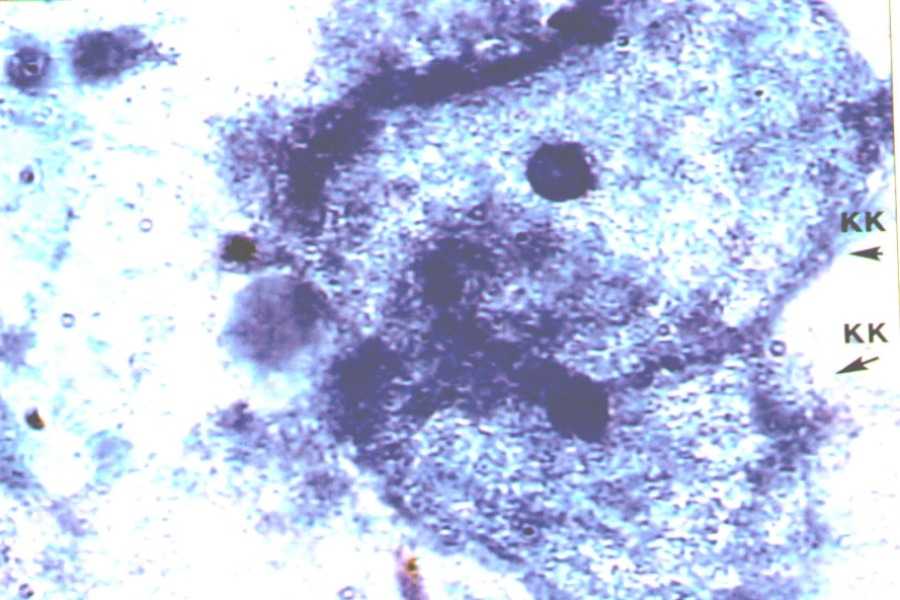

У женщин с БВ ключевые клетки — вагинальные эпителиальные клетки, покрытые Gardnerella vaginalis и палочками Mobiluncus, обнаруживаются в мазках выделений из влагалища. Наличие ключевых клеток в мазке считается наиболее надежным диагностическим критерием бактериального вагиноза.

Ключевые клетки

В прямом мазке вагинального секрета выявляется до 20% ключевых клеток. Этот факт имеет высокое диагностическое значение. Вышеупомянутая оценка одобрена международным сообществом. Чувствительность критерия наличия ключевых клеток в препарате прямого действия оценивалась в 80,7%, специфичность — 94,3%, при минимальной концентрации клеток 20% — чувствительность составляет 77,5%, специфичность — 95,4%.

Сравнительной основой для выявления ключевых клеток (золотой стандарт) является оценка мазка выделений из влагалища, окрашенных по Граму. При 400-кратном увеличении, чувствительность теста составляет 97%, а специфичность — 66%.